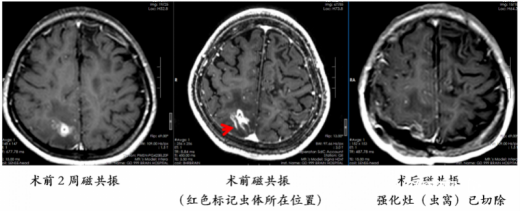

脑袋“长”虫,和饮食有关

根据复查影像,该院神经外八科二区王艮波主治医师发现虫体已转移到患者的右侧顶叶非功能区,“随访近4年,手术时机终于到了!”4月23日,神经外八科二区团队为患者行开颅手术,不仅顺利“生擒”一条20余厘米的虫子,还将“虫窝”(炎性肉芽肿)一并切除。